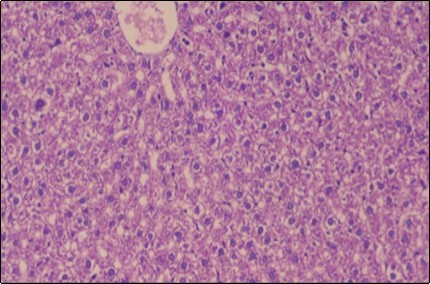

Effect of Ator, Fennel and Their Combination on the Liver of Obese Rats

The histological examination of the livers of control rats feeding standard diet showed normal architecture hepatocytes, blood sinusoid and central vein, figure 6. The rats which were fed on a (HFD), showed swollen hepatocytes with vacuolated cytoplasm filled with fatty infiltration, congested central vein and disappearance of blood sinusoids, figure 7. By comparison, the liver of rats that were treated by fennel after obesity and control mice observed nearly normal of the hepatocytes with eosinophilic cytoplasm, central vein and clear blood sinusoids and more bi-nucleated cells, figure 8. While examination of rats' liver that were treated by Ator and after the obesity appears, they showed mild fatty change in hepatocytes, few hepatocytes retain is eosinophilic cytoplasm and central vein figure 9. Liver of rats that were treated by fennel and Ator after obesity and control rats are showing nearly normal hepatocytes figure 10.

Figure 6.Photomicrogragh of liver section of control rat showing normal architecture Hepatocytes, blood sinusoid and central vein, (H&E) (40X).

Figure 7.Photomicrograph of liver section of obese rat showing swollen hepatocytes with vacuolated cytoplasm filled with fatty infiltration, congested central vein and disappearance of blood sinusoids, (H&E) (40X).